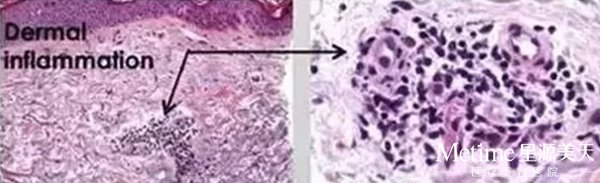

【皮秒治疗10分钟后】

真皮层之间形成了一个液泡!所以,为了治疗效果更佳,治疗后一定要注意防晒!

【皮秒治疗24小时后】

色素染色显示,包裹着黑色素的液泡处于真皮层之间,而皮下组织没有任何热损伤,这个色素液泡会通过人体的代谢细胞排除体外。